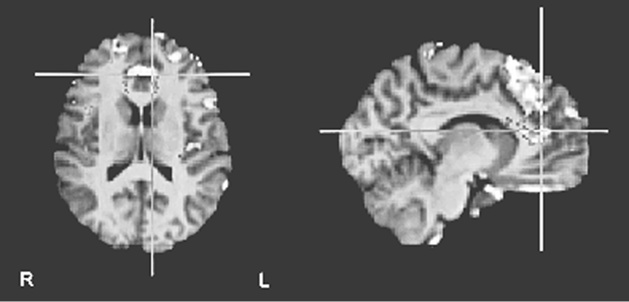

Но это было еще не все. Харрис обнаружил, что оценка «верю» сопровождалась усилением активности в вентромедиальной префронтальной коре (рис. 8.1a ниже) – участке мозга, отвечающем за совмещение факта и эмоции и изменение поведения в ответ на изменение обстоятельств (другими словами, уравновешивание «за» и «против»). «Не верю», в свою очередь, активизировала переднюю островковую долю мозга (рис. 8.1b) – участвующую в том числе и в кодировании негативных реакций, таких как боль и отвращение, и в оценке приятности различных вкусов и ароматов.

Иллюстрация к книге — Флипноз. Искусство мгновенного убеждения [i_053.jpg]

Рис. 8.1b. Осевое изображение (слева) показывает повышенную активность в нижней лобной извилине (в основном слева), в средней лобной извилине справа и в области островка с обеих сторон при оценке ложных утверждений по семи разным тематическим категориям. Изображение, напоминающее стрелку (справа), показывает повышение активности в верхней теменной доле, поясной коре и верхней лобной извилине (по материалам Харриса и др., 2008)